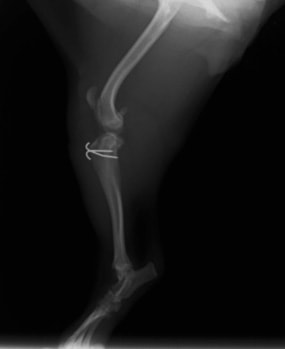

■ 症例20 ポメラニアン 8ヶ月 1.8kg

左右膝蓋骨脱臼 グレードⅢ

2ヶ月前から間欠的跛行が認められ、両膝の膝蓋骨脱臼整復術を行った。

手技は縫工筋及び内側広筋の解放、脛骨粗面の外側転位、滑車ブロック形造溝術、内外側関節包の縫縮を選択し実施した。

右側の膝蓋骨脱臼は上記手技で整復されたものの、左側はそれのみでは膝蓋骨が浮く様子が認められた。その為、PDS縫合糸にて膝蓋靱帯を1糸のみ縫合し、靱帯の縫縮を行った。

膝蓋骨脱臼は膝関節における膝蓋骨の内外側の脱臼と定義されるが、時として単純な内外の脱臼ではなく、膝蓋骨が大きく前方に浮き上がるように脱臼する場合がある。特にトイプードルやポメラニアンといった犬種に多く認められる。

内側脱臼に加えて前方への浮き上がりを矯正する為に、従来より脛骨粗面転移により膝蓋靭帯を外方と下方に引っ張り、固定する方法を選択する。膝蓋骨の前方への浮き上がりが軽度の場合は、従来法ではなく関節包の縫縮で対応していた。しかし、一部の症例で膝蓋骨の動きが悪くなり伸展機構が円滑に機能せずロボット様歩行になるケースがあった。

その為、膝蓋靭帯自体を縫縮する方法を採用した。この方法により、膝関節の伸展機構を妨げず膝蓋骨の軽度の浮きを矯正することが可能となった。

本症例の経過は良好である